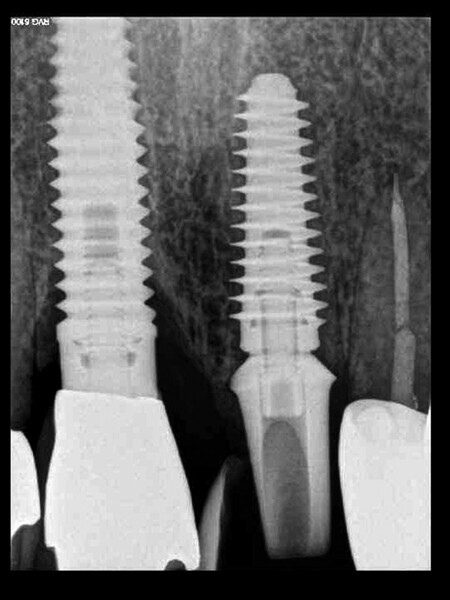

Fig. 13: The pre-op periapical radiograph revealed an existing implant-supported metal–ceramic restoration for the adjacent region #11.

Fig. 18: A periapical radiograph

with a drill in place confirmed that the apex length had been reached and that all the gutta-percha had been removed.